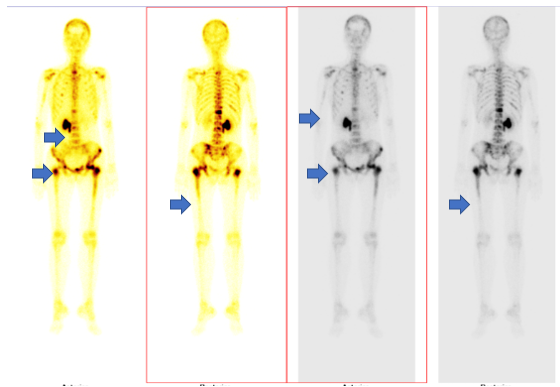

- Xạ hình xương: Hình ảnh tăng hoạt tính phóng xạ nhiều vị trí xương hộp sọ, nhiều đốt sống, xương cùng, xương cụt, nhiều xương sườn, xương cánh tay hai bên, xương chậu hai bên, xương đùi hai bên.

Hình 7

. Hình ảnh di căn xương đa ổ trên xạ hình xương (các mũi tên màu xanh)